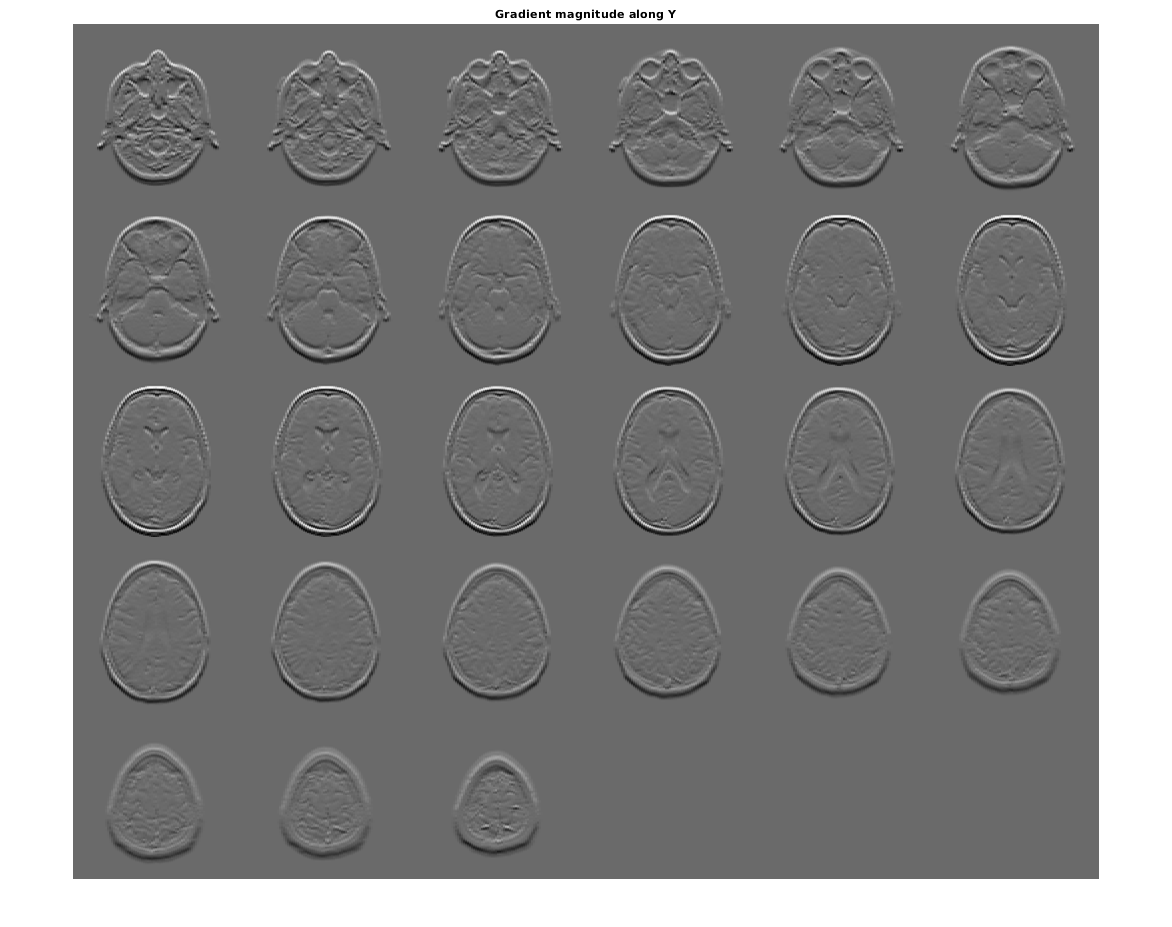

Визуализируйте направленные градиенты как монтаж.

figure, montage(reshape(Gy,sz(1),sz(2),1,sz(3)),'DisplayRange',[])

title('Gradient magnitude along Y')